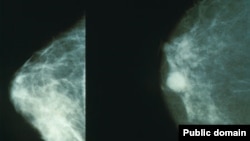

Иллюстрациялык сүрөт.

13-ноябрдан 20-ноябрга чейин Бишкектеги "Здоровье" менчик клиникасында маммолог жана онколог адистер аялдарды акысыз текшерүү акциясын өткөрүшүүдө.

Эмчек рагынын алдын алыш үчүн ультраүндүк кароо болуп, дарыгерлер аялдарга кеңеш берүүдө.

Кыргызстанда көкүрөк рагына чалдыккан аялдардын 39 пайызы оорусу өтүшүп кеткенде адиске кайрылууда. Жылына 600дөн ашуун аял ушул ооруга кабылып жатат. (BCh)